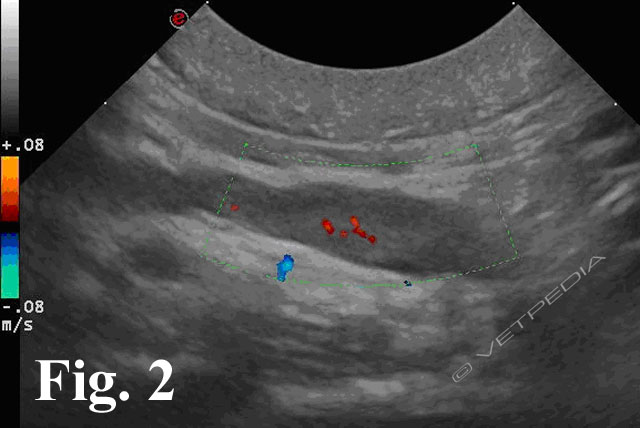

{{/_source.additionalInfo}}L’ecografia rappresenta una delle metodiche più sensibili per lo studio dei linfonodi addominali e permette di studiare la loro forma, le dimensioni, l’ecostruttura e l’ecogenicità. In tabella 1 sono riportati i linfonodi che drenano gli organi viscerali e le strutture parietali1. LINFONODI VISCERALI LINFONODI PARIETALI Lin